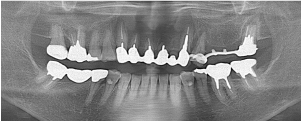

治療前のレントゲン

治療後のレントゲン

口腔内の金属をなくし、全体的に美しくしたいと希望されました。ホワイトニングから始め、すべての金属修復物をセラミックに置き換えました。上の前歯4本は形を整えてジルコニアオールセラミックで修復しています。右上5番は歯根破折していた為、抜歯してインプラント治療を行っています。